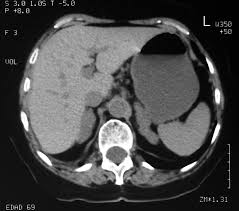

Adrenalitis tuberculosa

Es de rara presentación. La glándula adrenal es el órgano endocrino que más frecuentemente se afecta debido a un foco primario de TBC, como el pulmón, el riñón o el intestino. No se conoce claramente el tropismo del bacilo por las glándulas suprarrenales. Suele permanecer clínicamente latente durante décadas y en el momento del diagnóstico, cuando aparecen sus manifestaciones clínicas, la destrucción de las mismas puede llegar hasta 90%. Ocurre solo en 6% de los pacientes con tuberculosis activa. A pesar de la reducción de este porcentaje, el compromiso adrenal sigue siendo de difícil diagnóstico y se sabe que muchos casos no son notificados y solo son hallados en estudios posmórtem. La OMS predice un incremento continuo de la TBC y se estima que entre 19 y 43% de la población mundial está infectada por la micobacteria tuberculosis, la mayoría en forma de infección latente. Esto supone un enorme reservorio de individuos, entre los que son esperables nuevos casos. No se conoce claramente el tropismo del bacilo por las glándulas suprarrenales. Suele permanecer clínicamente latente durante décadas y, en el momento del diagnóstico, cuando aparecen sus manifestaciones clínicas, la destrucción de las mismas puede llegar hasta 90% y en la mayoría de los casos es bilateral, pero asimétrica.

El diagnóstico etiológico de certeza lo confirma la biopsia, aunque puede evitarse en caso de demostrar una infección tuberculosa activa en otra localización9,10. Cuando hay atrofia no hay consenso sobre la necesidad de comenzar tratamiento tuberculostático. Pero si están aumentadas bilateralmente, la pauta es similar a la TBC pulmonar. La recuperación glandular depende de la cantidad de tejido funcionante que en este caso fue precoz, a pesar de la resistencia a isoniacida por la mutación del gen katG, asociada en 60-90% de los casos de resistencias. El pronóstico es favorable y la supervivencia dependerá del proceso causal. Debido al incremento de la prevalencia de la TBC en el actual contexto de crisis económica y social global, debemos tener presente el probable origen tuberculoso en pacientes con insuficiencia suprarrenal. Su diagnóstico y tratamiento precoz son determinantes para preservar la función glandular.